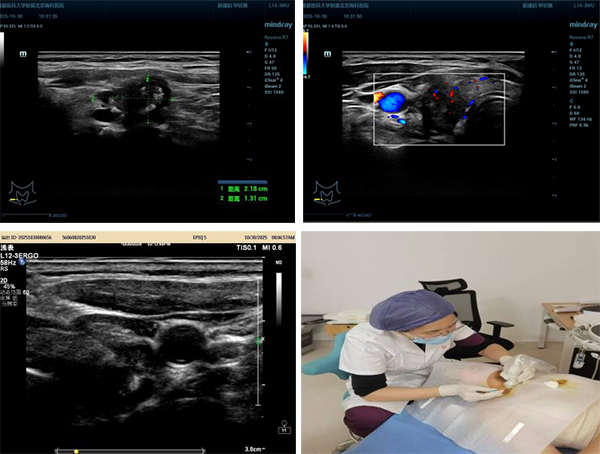

其中一例典型病例引发广泛关注:一位曾因颈部淋巴结结核接受7个月规范治疗的老年患者,在复查时意外发现甲状腺右叶后方存在一个约2.2×1.3厘米的低回声结节,伴有钙化。超声医学科主任王金萍凭借丰富经验,判断该病灶并非结核复发,而高度疑似甲状腺原发恶性肿瘤。随即在超声实时引导下完成细针穿刺,病理结果确诊为甲状腺乳头状癌,并检出BRAF V600E基因突变——这一关键信息为后续个体化治疗提供了重要依据。

医生在超声实时引导下,使用极细穿刺针吸取结节内少量细胞,送至病理科进行分析。该方法创伤小、安全性高、诊断准确,目前已在临床工作中广泛应用。